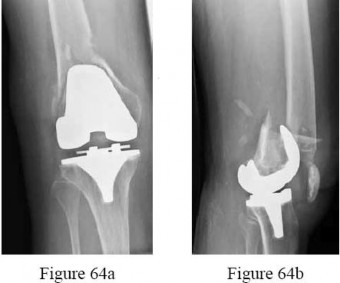

-are the radiographs of a 62-year-old woman who is seen in the emergency department after a fall to a flexed knee. She underwent posterior-stabilized total knee arthroplasty 6 years ago. She has no other injuries and was previously a community ambulatory without assistance. What is the most appropriate treatment?